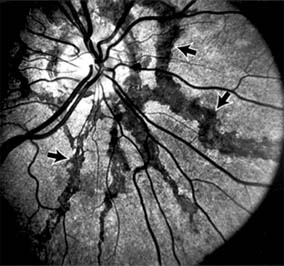

Figure 10-9

Figure 10-9: Multiple angioid streaks (arrows) extend from the optic nerve. (Courtesy of University of California, San Francisco.)

Angioid streaks appear as irregular, jagged tapering lines that radiate from the peripapillary retina into the macula and peripheral fundus (Figure 10-9). The streaks represent linear crack-like dehiscences in Bruch's membrane. The lesions are rarely noted in children and probably develop in the second or third decade of life. Early in the disease the streaks are sharply outlined and red-orange or brown. Subsequent fibrovascular tissue growth may partially or totally obscure the streak margins.